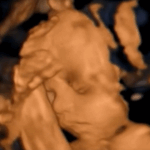

エコー写真(@piyopiyosan723さんより提供)